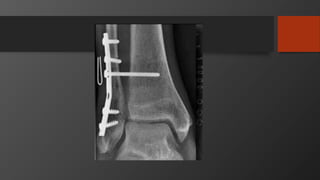

Ankle Fractures

Imaging

• AP, Lateral

• Mortise view

• CT scan

• Especially posterior malleolus

Initial treatment- reduce dislocations